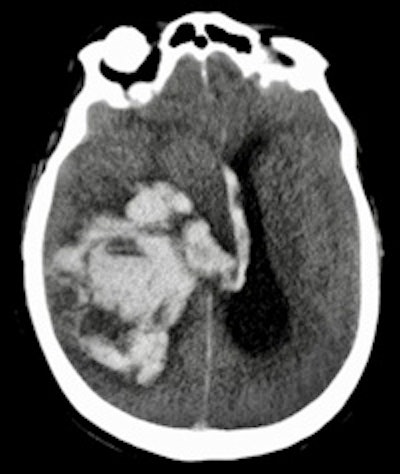

Dr. Wolter Oosterhuis from Rotterdam.The advantages of the minimally invasive method included perfect depiction of pathologies such as pneumonia, sometimes overlooked in traditional autopsy due to the thickness of organ slices. In addition, MRI appeared highly sensitive for guiding tissue sampling in the diagnosis of acute myocardial infarction. However, the minimally invasive approach had trouble identifying bowel ischemia, because it is difficult to spot early necrosis in the bowel wall or obtain samples when it can be seen.